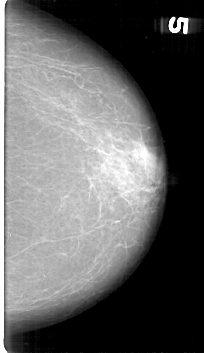

D_4136_1.LEFT_MLO

LEFT_MLO LINES 5251 PIXELS_PER_LINE 3181 BITS_PER_PIXEL 12 RESOLUTION 43.5 NON_OVERLAY